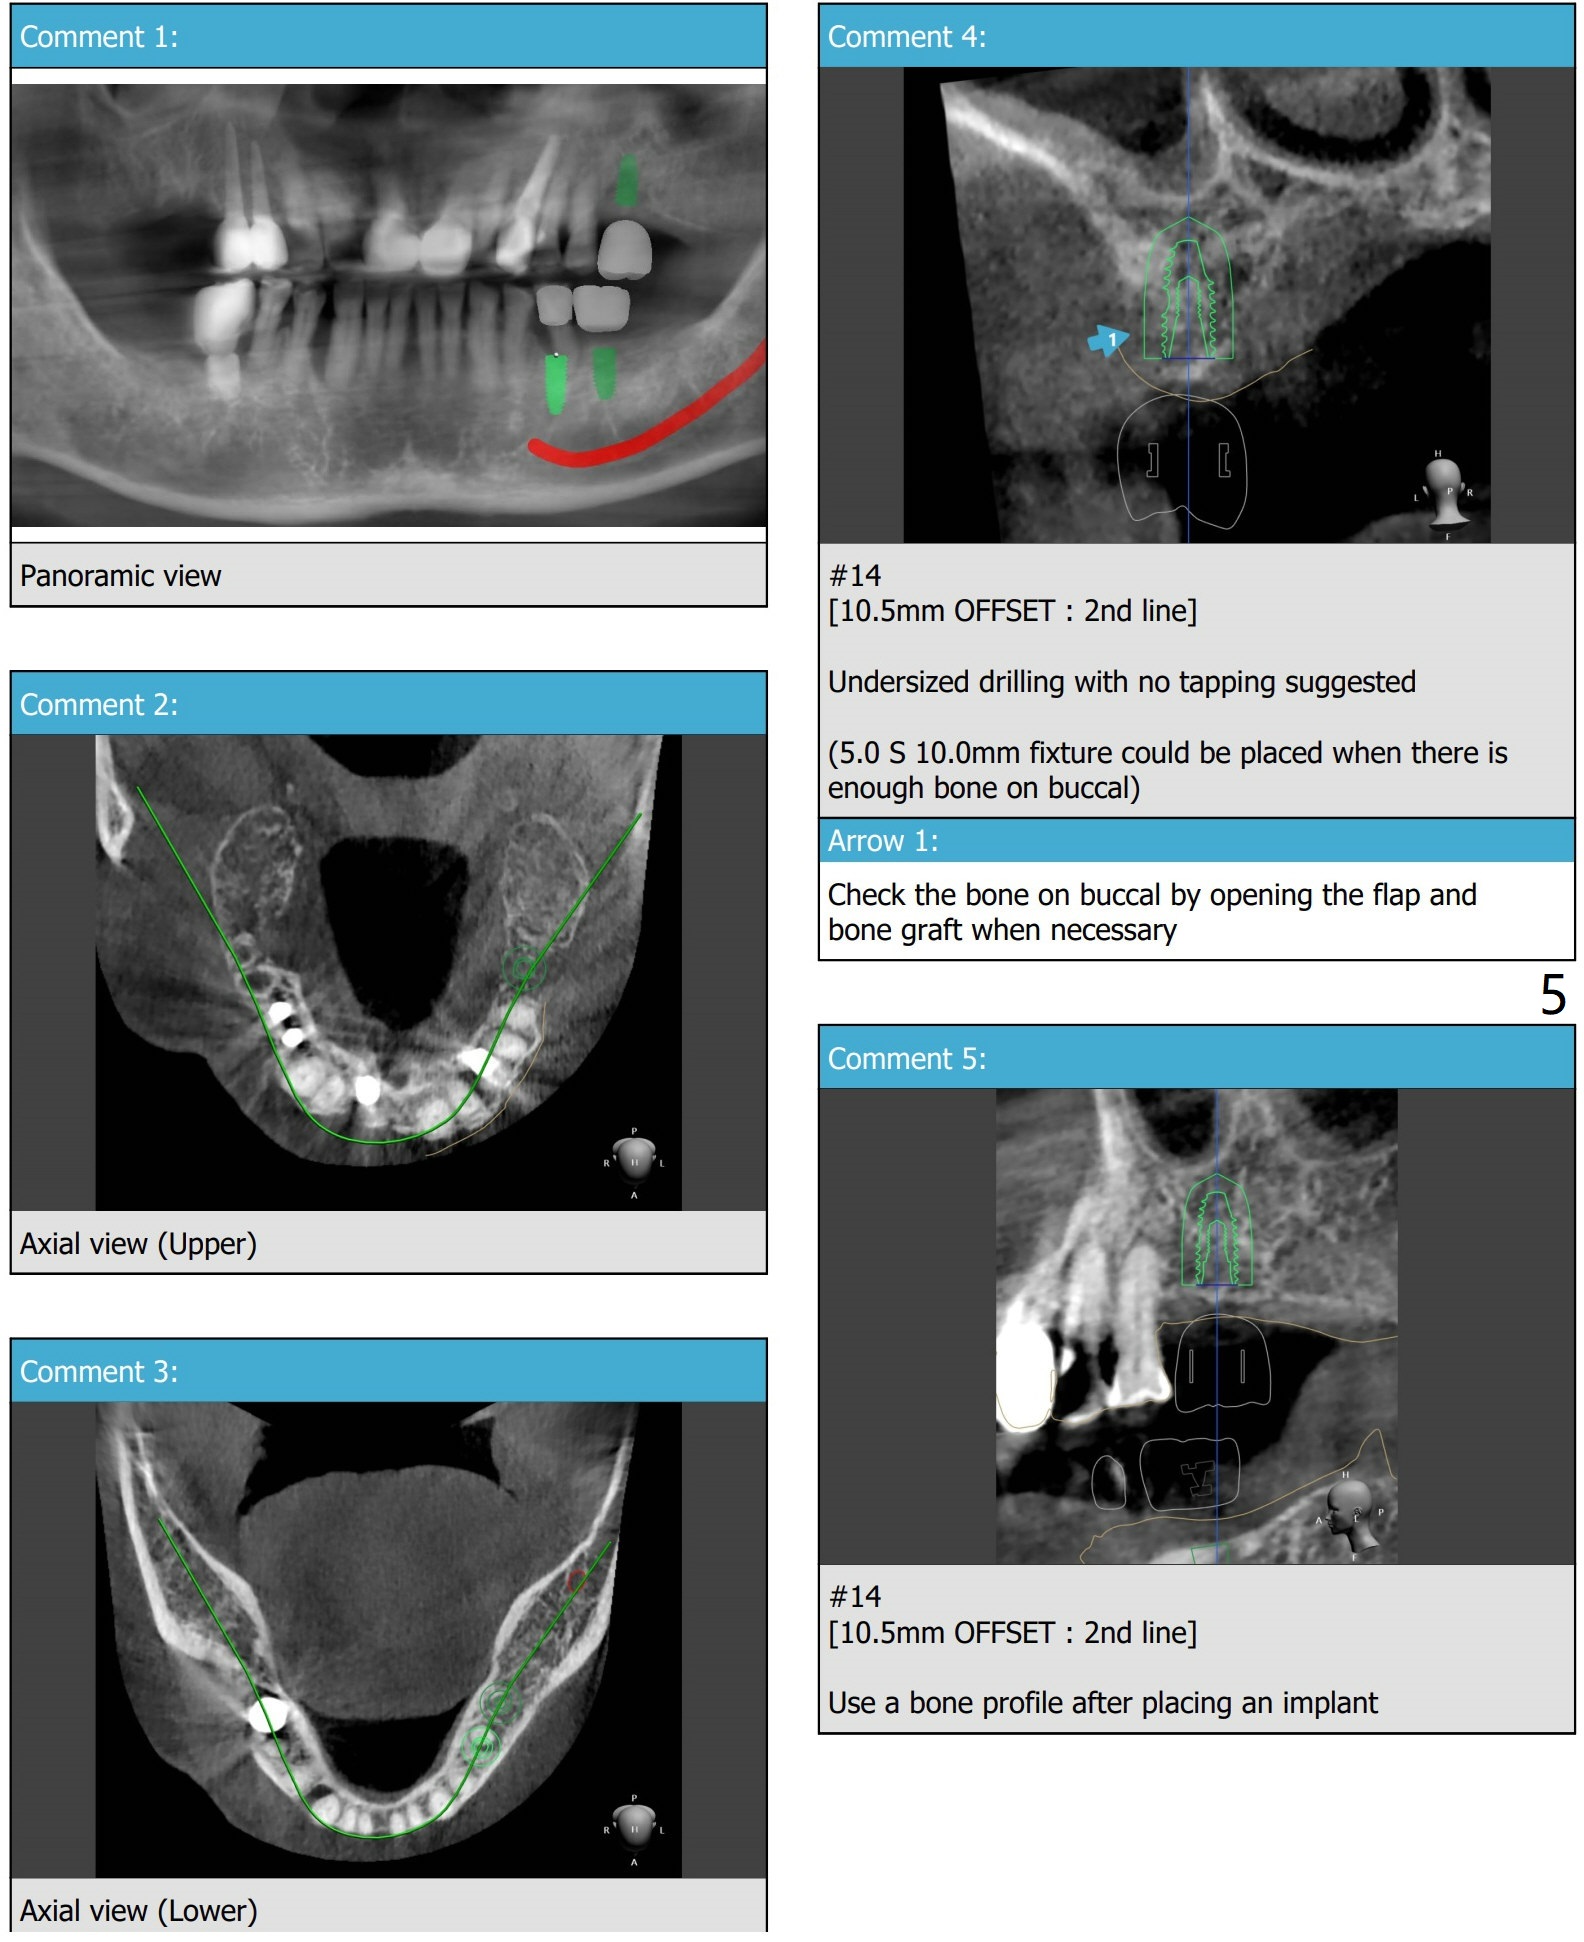

#14 Indistinct Buccal Plate

A 80-year-old man requests implants to replace his missing teeth. #14 incision for bone graft. PRFx2. Tatum 14 mm for #14 and 19, 14 or 17 mm for 20. Prepare taps.